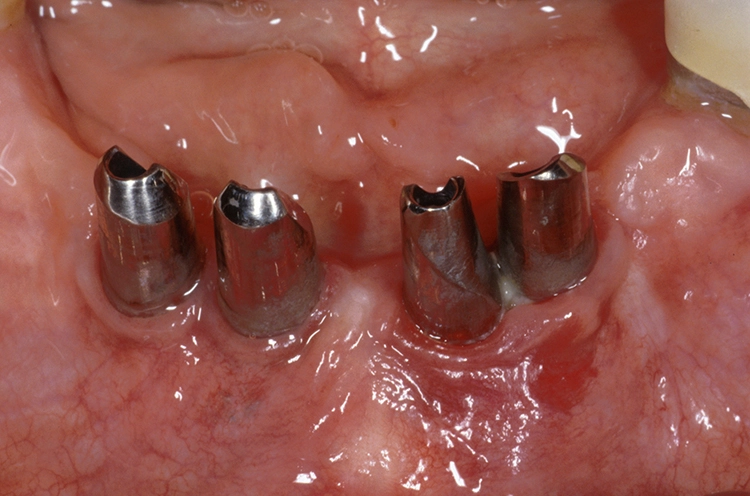

Und was wäre die Alternative? Aus unserer Sicht ist es das 1-teilige Zirkonoxidimplantat (Abb. 2).

Wirkliche Aussagen über die Eignung eines Implantates liefern nur klinische Studien. Es liegen wenige Langzeitdaten mit 1-teiligen Implantaten aus Zirkonoxid vor, dagegen keine zuverlässigen Daten mit den aktuell erhältlichen 2-teiligen Implantaten. Gut dokumentiert im Rahmen prospektiver klinischer Studien sind die 1-teiligen Implantate vom Typ Pure (Straumann, Basel, Schweiz) [9], Ziraldent (Metoxit, Thayngen, Schweiz; Vertrieb heute unter dem Produktnamen Fairwhite durch Fairimplant, Bönningstedt, Deutschland; im Folgenden immer als „Fairwhite“ bezeichnet) [29] sowie ceramic.implant (VITA, Bad Säckingen, Deutschland) [4].

In zahlreichen Reviews wird bescheinigt, dass Zirkonoxidimplantate klinisch genauso erfolgreich sind wie Titanimplantate [2,15,20,21,33,35,49]. Wichtig ist aber, dass man sich die Ergebnisse einer klinischen Studie sehr genau im Detail anschaut, weil man viel mehr herauslesen kann als nur Erfolg oder Misserfolg und die Lage des periimplantären Knochenniveaus. Unsere Forschung baut im Wesentlichen auf den Erfahrungen mit dem ceramic.implant auf.